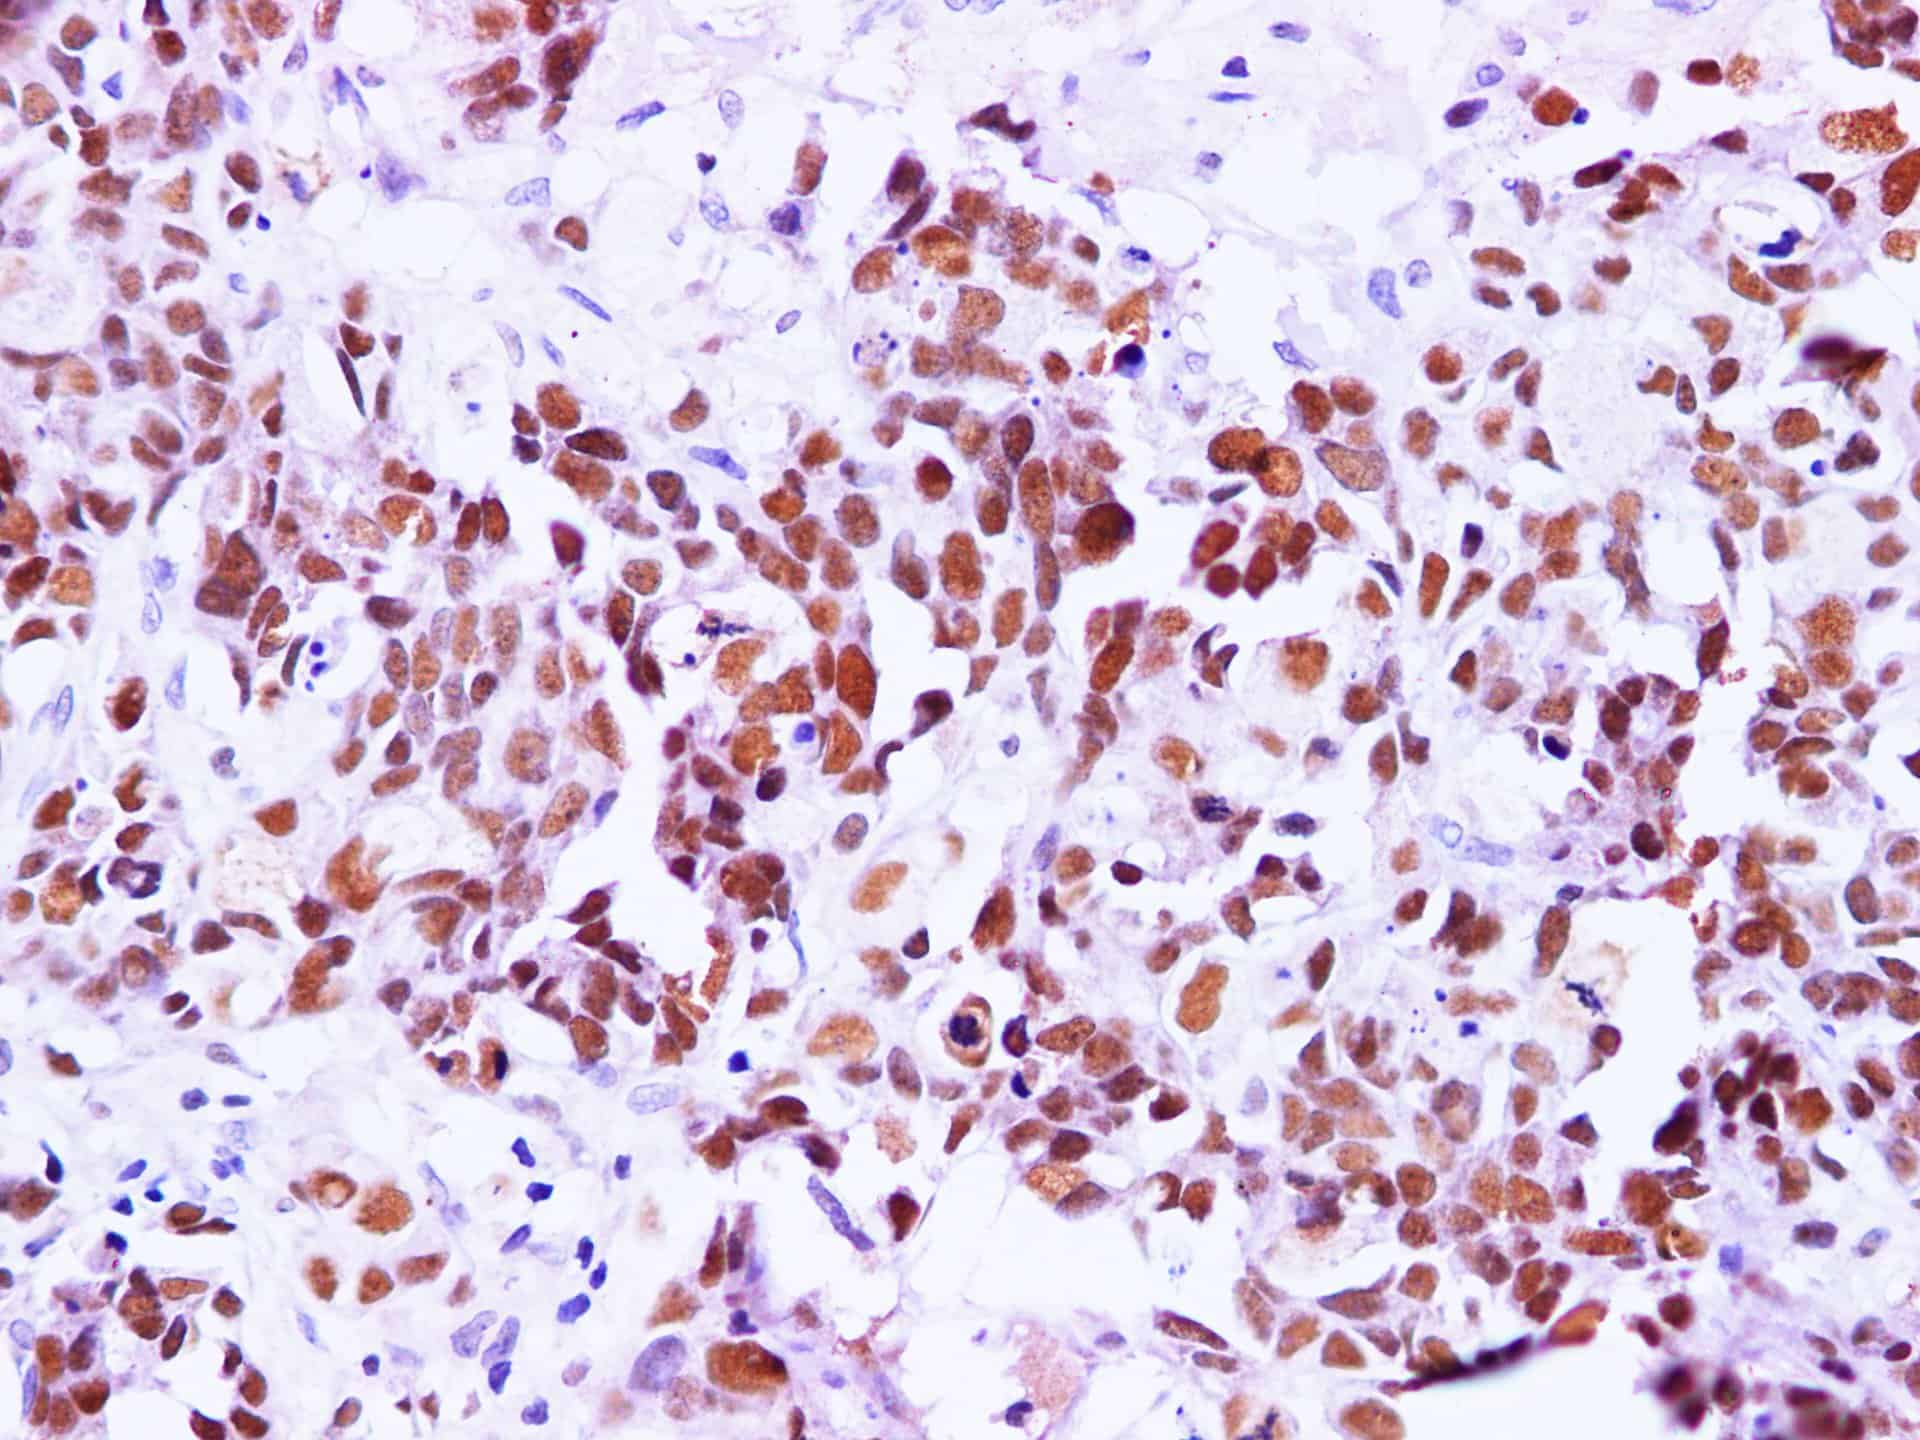

Immunohistochemistry of paraffin-embedded Human breast cancer using BRCA1 Polyclonal Antibody at dilution of 1:100